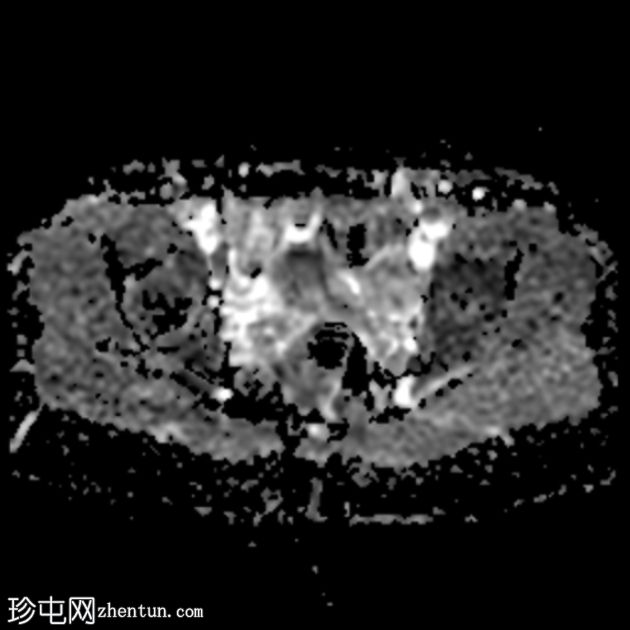

轴位

ADC序列

该病例的盆腔器官MRI表现与患者年龄(14岁)相符,子宫位置正常,分区解剖结构正常,双侧卵巢大小及卵泡活动均正常,未见囊性或实性肿块。

此外,MRI还意外发现子宫肌层局灶性病变,T2信号低,易被误诊为子宫肌瘤。然而,该病变在后续序列中消失,符合短暂的生理性子宫肌层收缩所致。